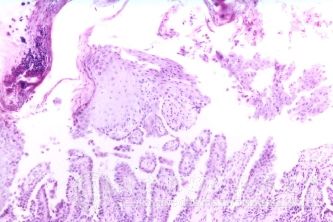

北京京城皮肤医院指出,自身敏感性皮炎的病因:目前尚不十分清楚。发病前,在皮肤某部常有湿疹样损害,由于过度搔抓、外用药物刺激或并发化脓感染而使原有损害恶化,红肿。皮肤上平行排列的糜烂、渗出明显增加,加之处理不当,创面不洁,组织分解物、细菌产物等形成一种特殊的自身抗原,被吸收发生致敏作用而引起全身泛发。